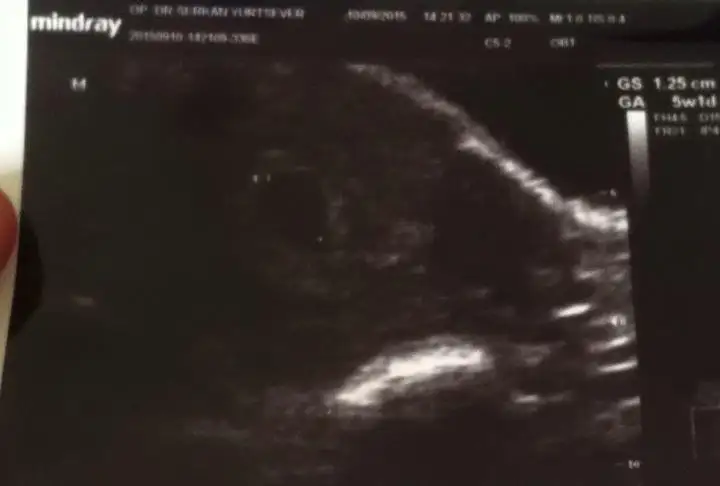

AMIN CANIM HEPIMIZIN KORKUSU BU SANIRIM RABBIM INS HIC BIRIMIZE GOSTERMEZ YASATMAZ BU ACIYIaynı durum ve korku bende de var 5+1 kese var hatta kesem 4 haftalıkken göründü 4 mm di dün 12 mm olmuş ama bebiş yok henüz daha erken dedi doktor ama insan endişeniyor işte boş gebelik korkusu bende de cokAllah ım inş. öyle bişi olmaz sağlıklı sıhhatli kalp atışlarını duyar sonrada kucagımıza alırız bebişlerimizi

doktor mu 7+2 diyor canım.. peki alttan ultrasyonla bakıldımı? sadece karından mı bakıldı ?çok sağol inşallah geçer. benim 7+2 hamile diyor kese en son bu salı gittim 1.77 cm o boş gebelik lafını duydum ya kaç haftalık ne zaman doğum olur hiç bir şey sormadım güya kalp atışını duyacaktım.